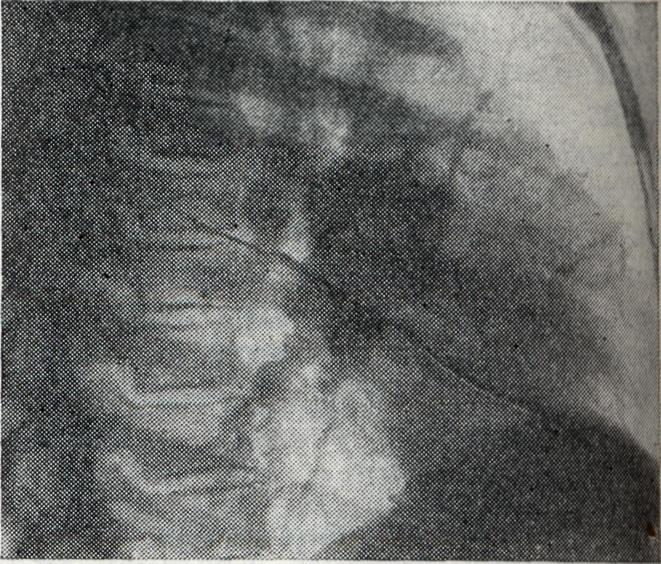

Рис. 4.

Правосторонний инфильтративный бронхаденит: видна междолевая уплотнённая плевра и инфильтративно расширенный и уплотнённый корень правого лёгкого; контур корня нечёткий (рентгенограммы: 1 — прямая проекция; 2 — боковая проекция).

При инфильтративной форме Б. (рис. 4, 1 и 2) возникают воспалительные изменения в лёгочной ткани за капсулой лимф, узлов. Поэтому весь корень или отдельные его участки увеличиваются, тень корня уплотняется. Линия наружного контура корня делается неясной и размытой от воспалительного уплотнения перибронхиальной, периваскулярной и межуточной ткани лёгкого. Опухолевидная и инфильтративная формы Б. при благоприятном течении процесса заканчиваются Рубцовым уплотнением корней лёгких (рис. 5); в отдельных группах лимф, узлов наблюдаются и явления кальцинации (петрификаты): отдельные мелкие плотные тени, иногда сгруппированные в более крупные конгломераты. Дифференцирование сосудистой тени от кальцинатов в лимф, узле проводится при многоосевом просвечивании: тень от петрификата в корне легкого при поворотах исследуемого не выходит за его границы, интенсивность ее не изменяется; тень от осевой проекции сосуда при движении больного вытягивается вначале в овал, а затем в продольную линейную проекцию. Кроме того, тени кальцинированных лимф, узлов редко бывают монолитно плотными и правильной округлой формы с ровными краями, что более характерно для осевых проекций сосудов.